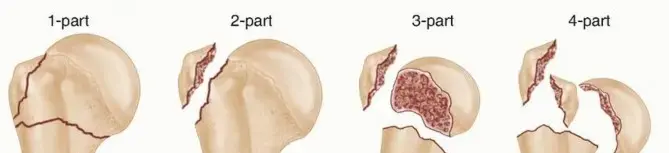

تصنيف الكسور (تصنيف نير Neer Classification)

يُعد تصنيف نير أحد أكثر الأنظمة استخدامًا لتقييم كسور عظم العضد القريب. يقسم هذا التصنيف الكسر بناءً على عدد الأجزاء الرئيسية المتأثرة (رأس العضد، الحدبة الكبرى، الحدبة الصغرى، وجسم عظم العضد) ومدى إزاحتها. يُعتبر الجزء "مُزاحًا" إذا كان هناك إزاحة تزيد عن 1 سم أو زاوية تزيد عن 45 درجة:

* جزء واحد (One-part): جميع الشظايا في مكانها أو بإزاحة بسيطة جدًا.

* جزأين (Two-part): جزء واحد مُزاح بشكل كبير (مثل كسر في العنق الجراحي أو الحدبة الكبرى).

* ثلاثة أجزاء (Three-part): جزأين مُزاحين بالنسبة للثالث.

* أربعة أجزاء (Four-part): جميع الأجزاء الأربعة مُزاحة. يحمل هذا النمط أعلى خطر للإصابة بالنخر اللاوعائي.

يساعد هذا التصنيف الأستاذ الدكتور محمد هطيف في تحديد شدة الكسر وتوجيه خطة العلاج المناسبة لكل مريض.